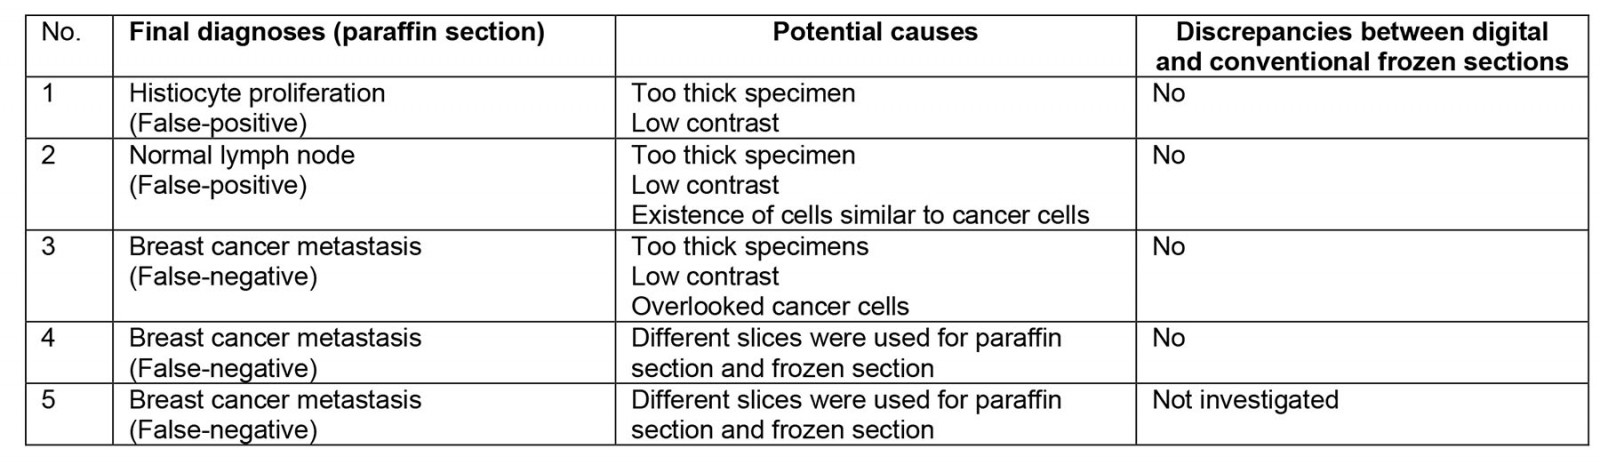

Among these, positive and negative cases in the remote consultations were 8 (18%) and 37 (82%), respectively. Compared to the permanent specimens, the overall accuracy ratio was 89% (40/45), with the positive and negative predictive values being 67% (6/9) and 94% (34/36). Supplementary table 1 shows breakdowns of cases where paraffin section and frozen section of sentinel lymph nodes differed. An illustrative example of these discrepancies is shown in Figure 1, where a false positive diagnosis occurred during a remote intraoperative frozen section consultation of a sentinel lymph node biopsy. Upon review of this case, it was determined that prominent histiocytic proliferation had been mistakenly identified as cancer cells.

We reviewed a total of four out of the five cases for which there were discrepancies between diagnosis of paraffin section and frozen section of sentinel lymph nodes. After the review, it was determined that there were no differences in diagnosis between the digital and traditional frozen sections of sentinel lymph nodes (Supplementary table 1). Furthermore, both the quality of the frozen sections and the images obtained from the monitor for the digital slides were excellent. There were no issues such as tissue wrinkles, tissue overlap, tissue folding or air entrapment in the microscopic preparation. There was no apparent difference in diagnostic accuracy between the two systems.

Figure 1: Microscopic image (hematoxylin–eosin stain) of extracted lymph node from case 1 (200× magnification).

Figure 1: Microscopic image (hematoxylin–eosin stain) of extracted lymph node from case 1 (200× magnification).